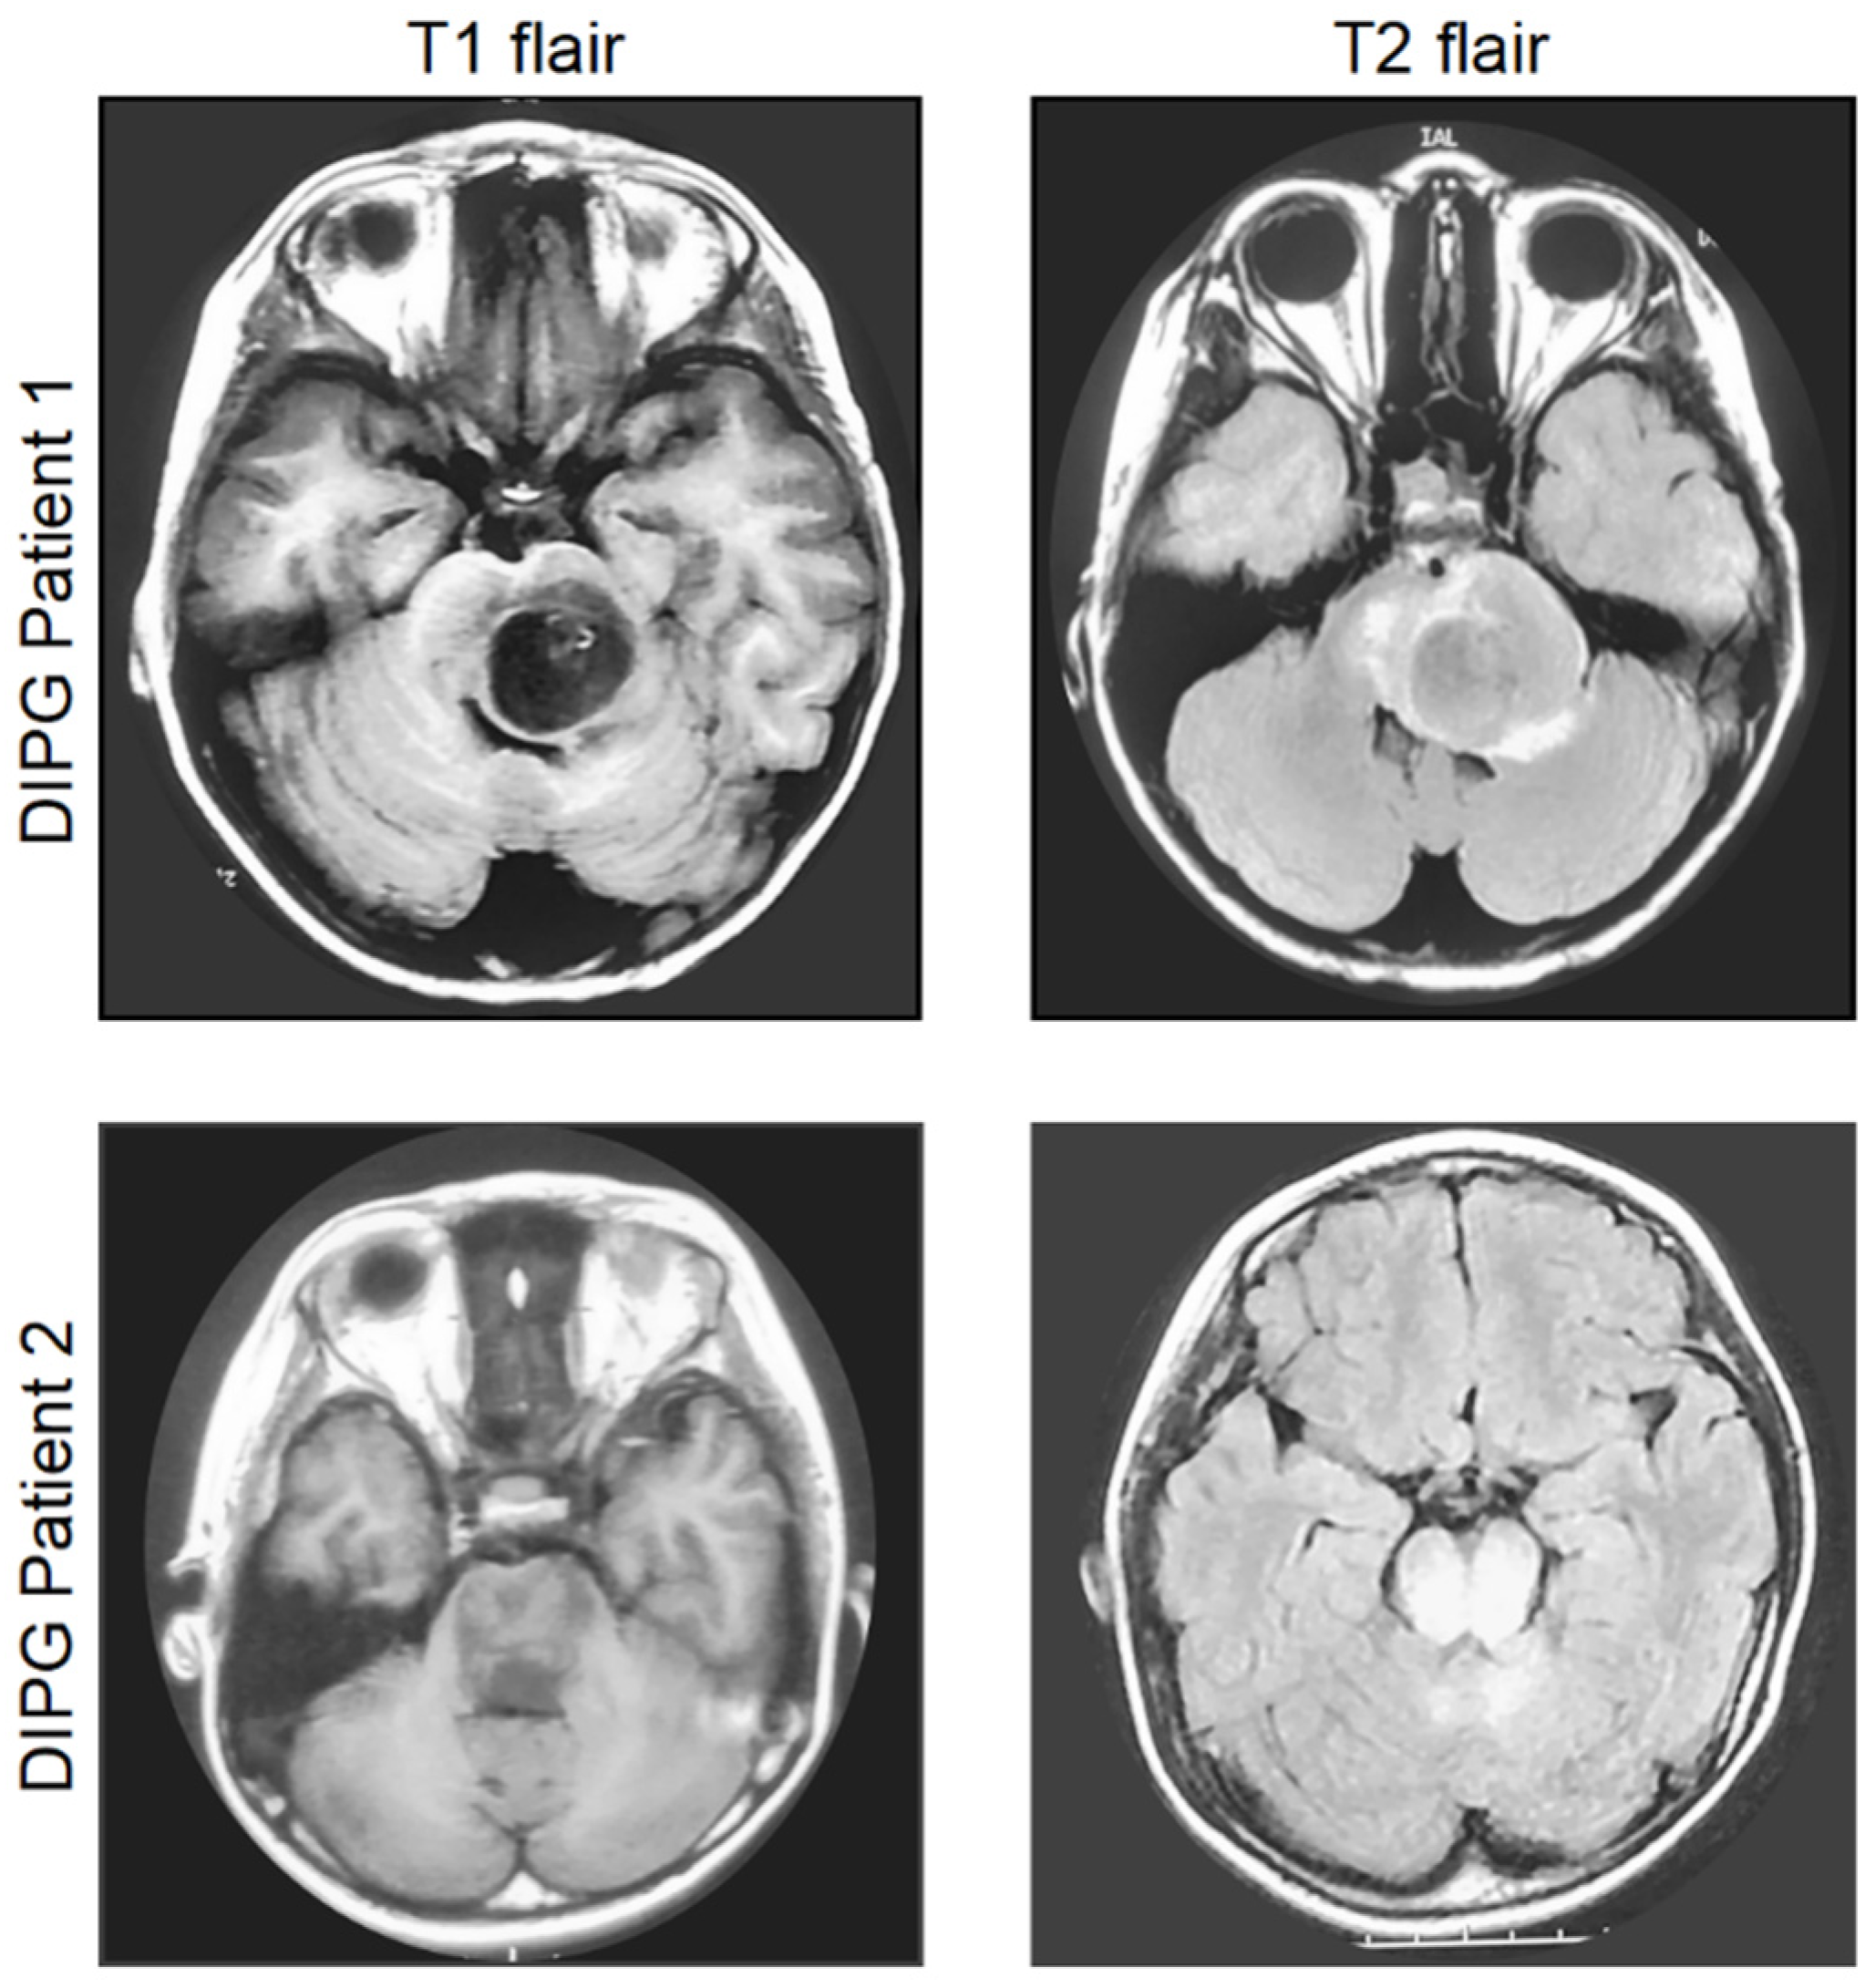

2. Diagnosis, Current Management, and Molecular Characteristics of DIPG